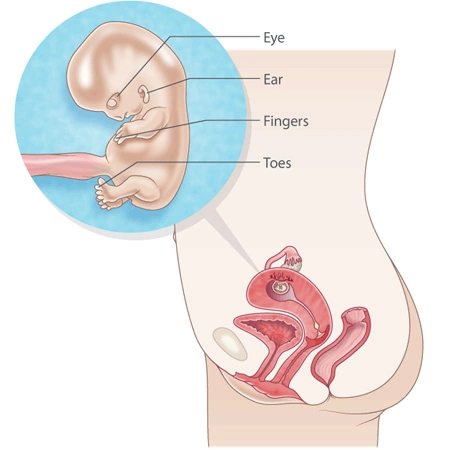

At week 10 of pregnancy, your baby is still tiny but growing rapidly. Floating safely in the warm amniotic fluid, your little one now measures about three centimeters in length. The body is becoming more proportionate— the head no longer looks oversized compared to the rest of the body.

Ankles and wrists have formed, and the tiny fingers and toes are now clearly visible. It’s hard to imagine, but your baby already looks more human than ever before.

During week 10, your baby’s internal organs are coming to life. A routine ultrasound may show that the yolk sac has disappeared and the umbilical cord, which connects the placenta to your baby, is now fully visible.

The intestines, still partly inside the cord, are moving gradually into the abdomen and will soon be covered by skin. Meanwhile, several vital organs start functioning:

Your baby’s lungs are developing, and tiny bones—even within the fingers—are forming. Bone marrow cells will soon start producing red blood cells, a task previously handled by the liver and spleen.

Facial features are becoming more defined; buds of baby teeth may be forming, and your little one can now open the mouth and move the tongue—though not long enough for any tongue-out gestures yet!